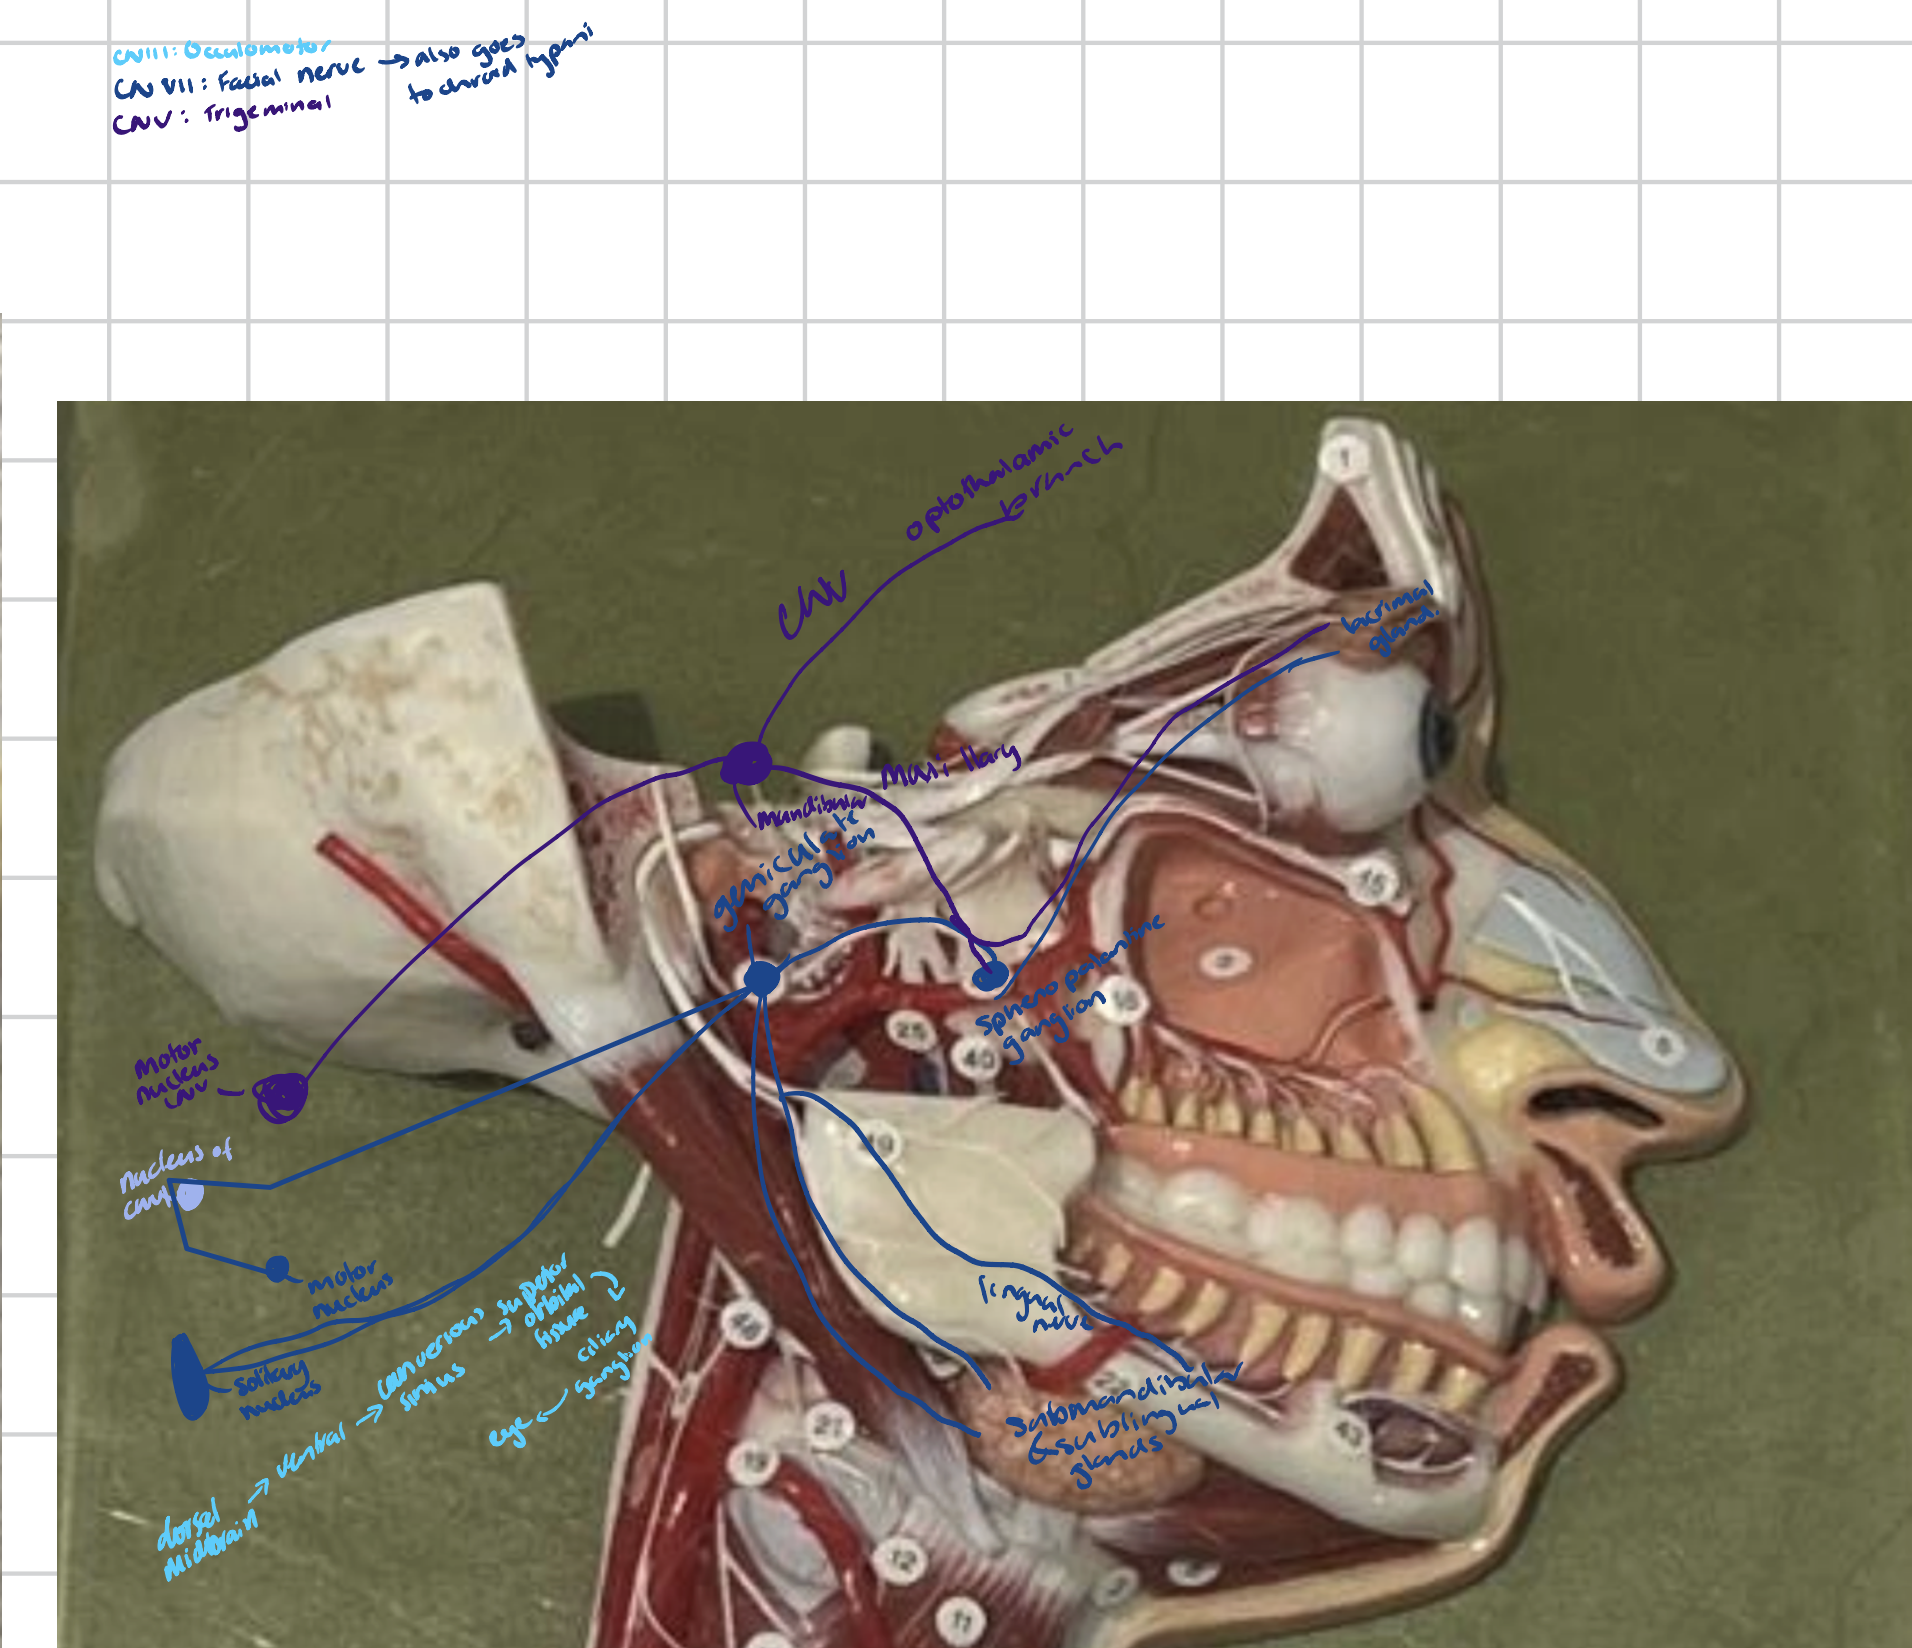

Trigeminal/Gasserian ganglion

A large, crescent-shaped sensory ganglion of the fifth cranial nerve (CN V) that is located in the middle cranial fossa.

Contains cell bodies for the three main branches of the trigeminal nerve.

Eye Muscles

Eye

Upper palpebra

Lacrimal caruncle

Medial commissure

Palpabral fissure

Lacrimal gland

Superior and inferior lacrimal canals

Lacrimal sac